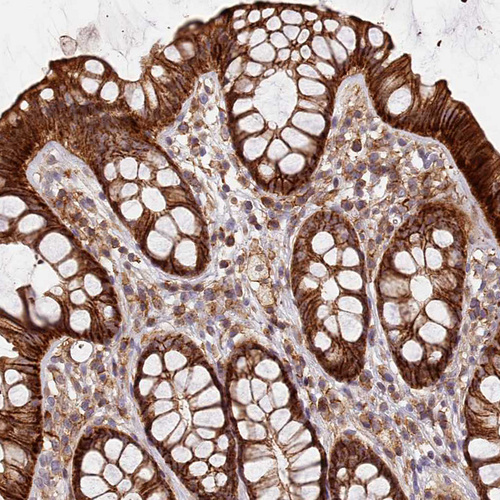

Immunohistochemical staining of human Kidney shows moderate cytoplasmic positivity in cells in tubules.